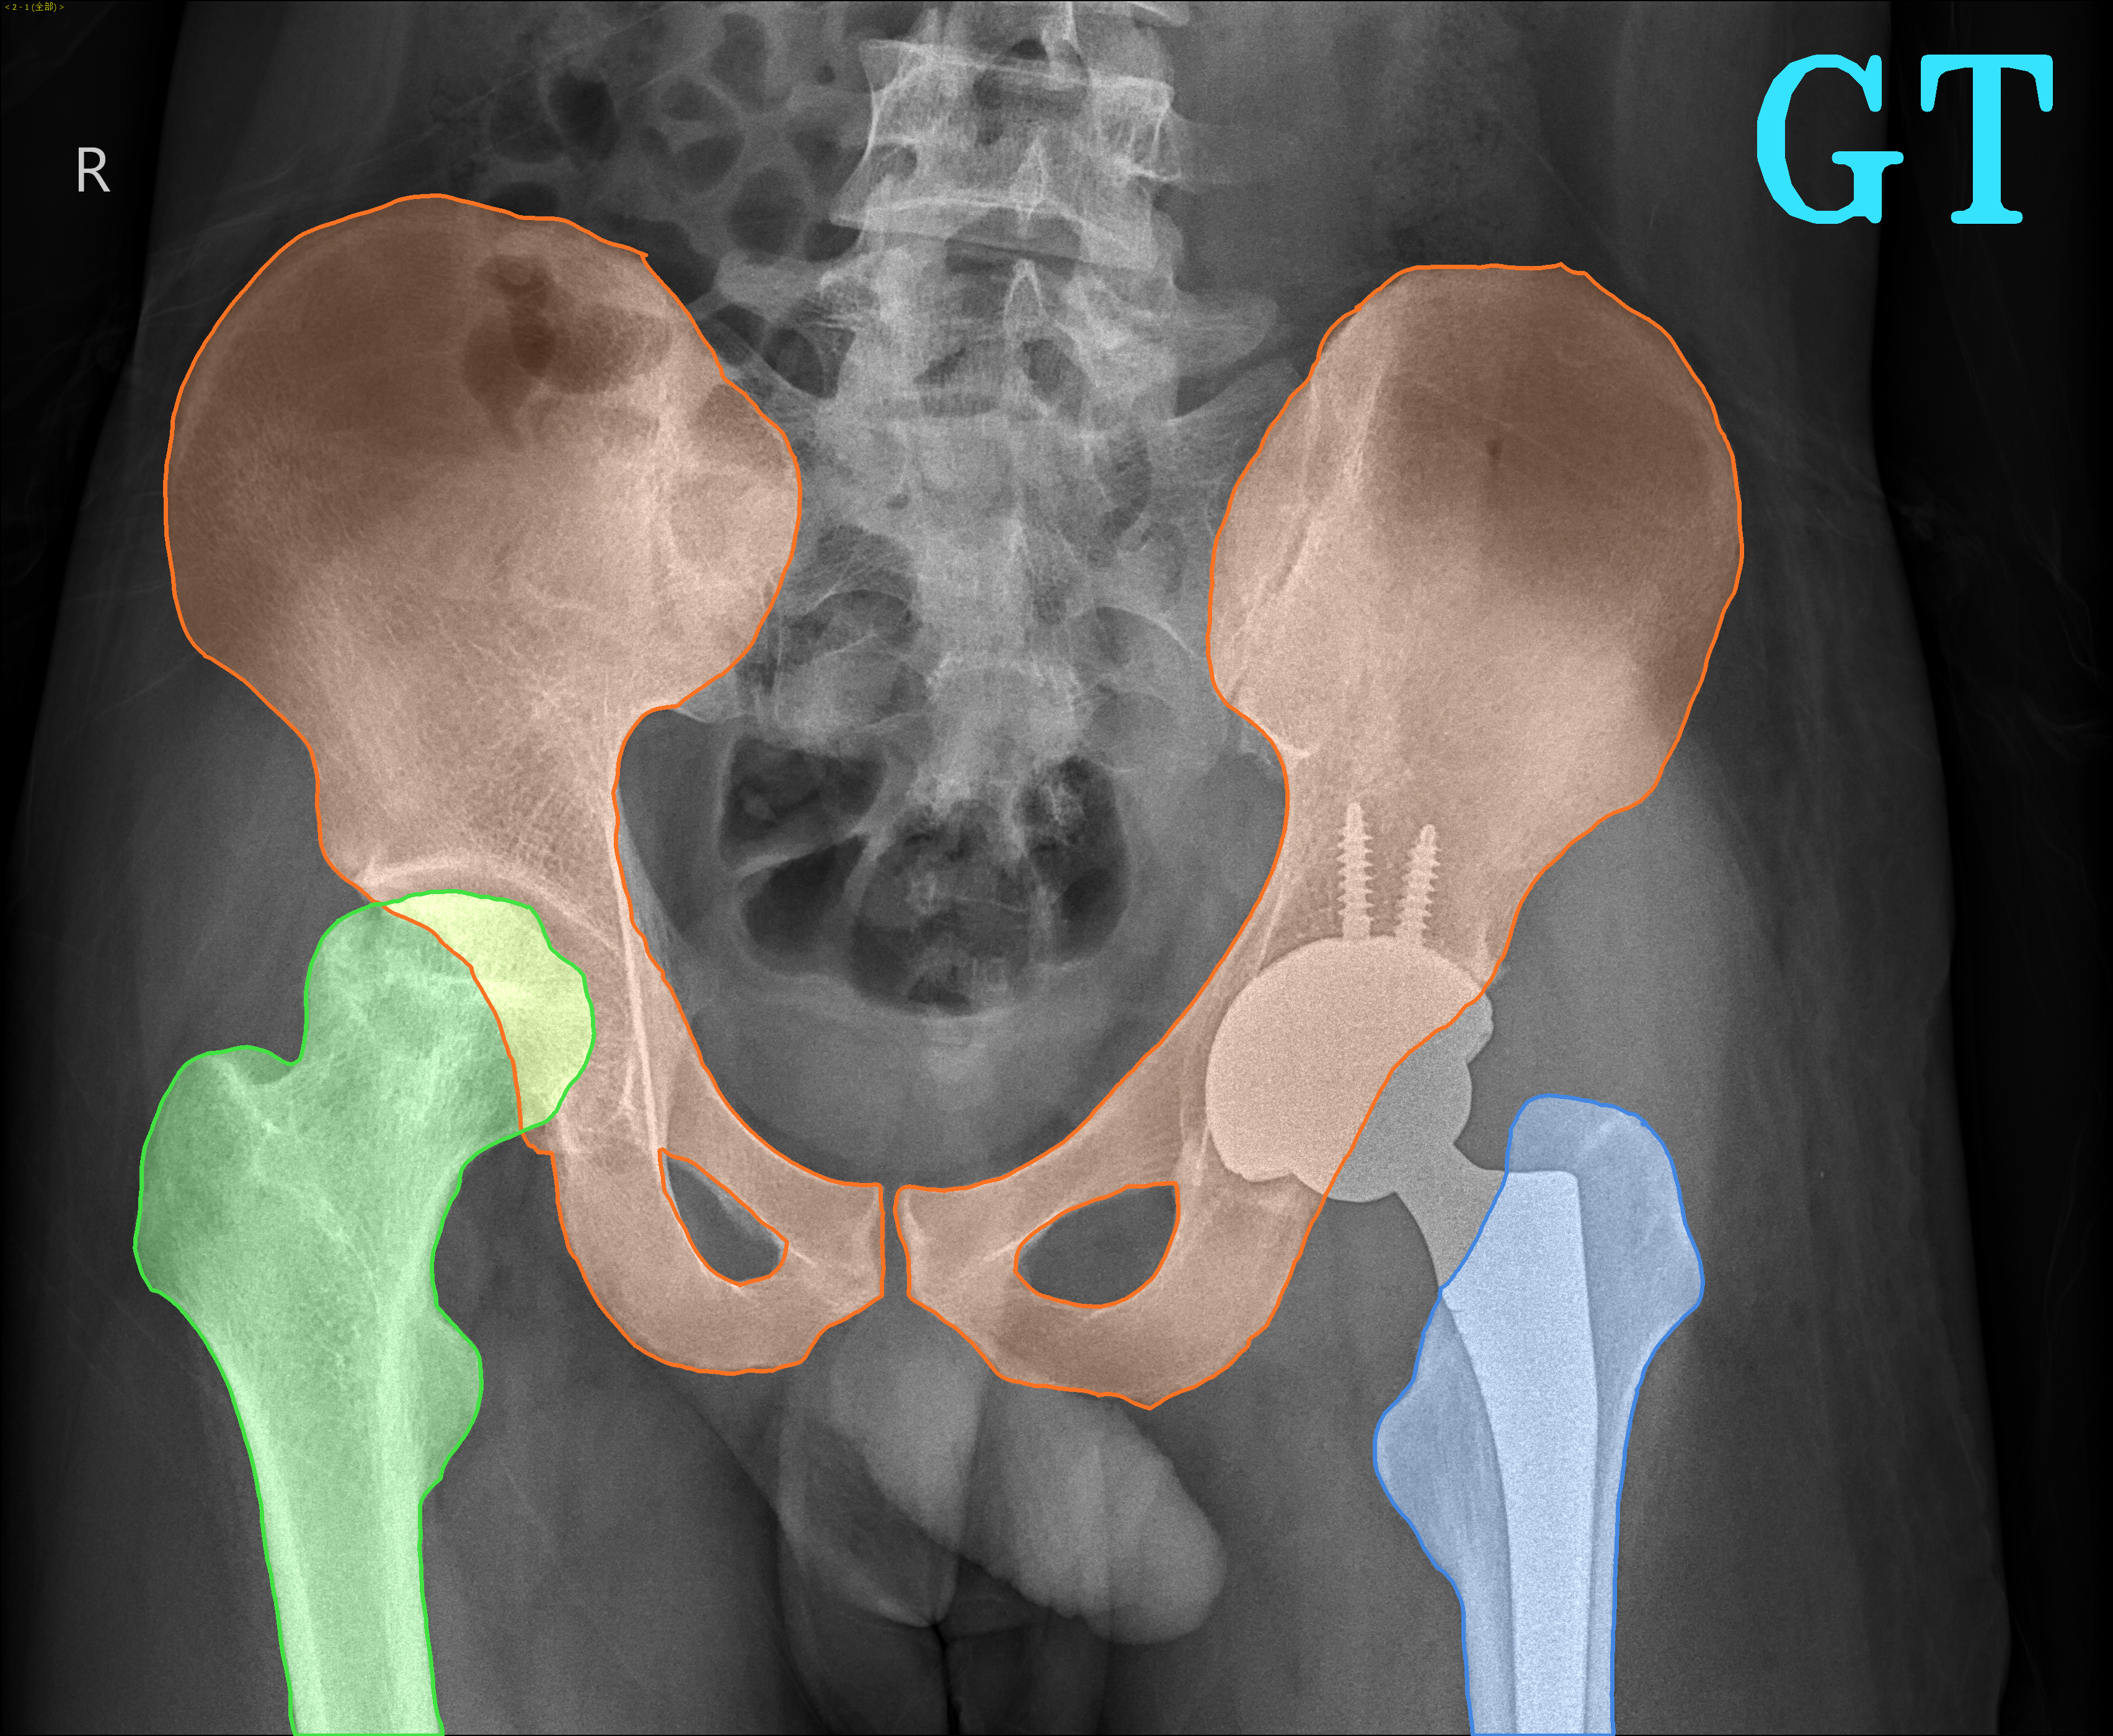

TransFuse is evaluated on both 2D and 3D datasets to demonstrate the effectiveness. As different medical image segmentation tasks serve different diagnosis or operative purposes, we follow the commonly used evaluation metrics for each of the segmentation tasks to quantitatively analyze the results. Selected visualization results of TransFuse-S are shown in Fig. 2.

Results of Hip Segmentation. Tab. 3 shows our results on hip segmentation task, which involves three human body parts: Pelvis, Left Femur (L-Femur) and Right Femur (R-Femur). Since the contour is more important in dianosis and THA preoperative planning, we use Hausdorff Distance (HD) and Average Surface Distance (ASD) to evaluate the prediction quality. Compared to the two advanced segmentation methods [33, 28], TransFuse-S performs the best on both metrics and reduces HD significantly (30% compared to HRNetV2 as well as 34% compared to Unet++ on average), indicating that our proposed method is able to capture finer structure and generates more precise contour.

| Hip Segmentation | |||

|

|

|

|